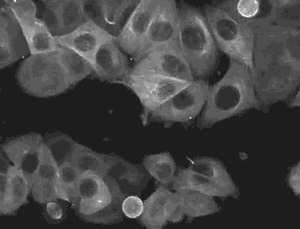

△干细胞具有分化成大多数细胞、组织、甚至器官的能力